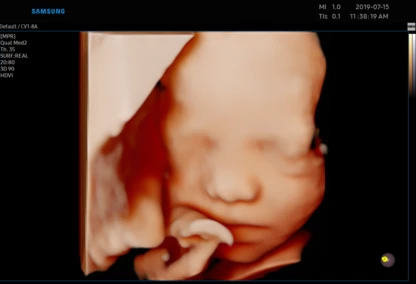

Każdą kobietę w ciąży otaczamy kompleksową opieką, czuwając nad jej zdrowiem oraz prawidłowym rozwojem płodu. Podczas regularnych wizyt, zlecamy odpowiednie badania laboratoryjne. Korzystając z najnowszej generacji aparatu USG, przeprowadzamy bardzo dokładną diagnostykę obrazową – łącznie z USG 3D/4D płodu.